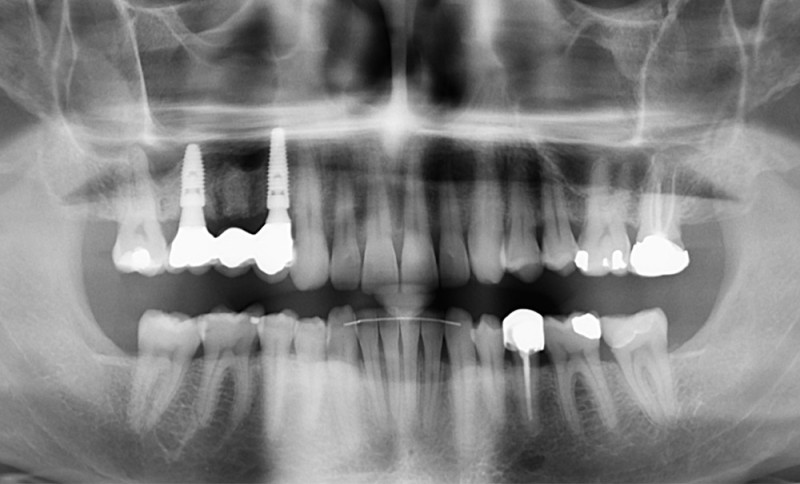

Présentation du cas clinique (fig. 1 à 3)

Le patient, âgé de 58 ans, présente un encombrement dentaire mandibulaire de 5 mm dans un contexte squelettique hypodivergent.

À la radiographie panoramique, on constate une lésion apicale sur 15 et une atteinte inter radiculaire sur 16 ainsi qu’une légère rotation de 21 sans gêne pour le patient.